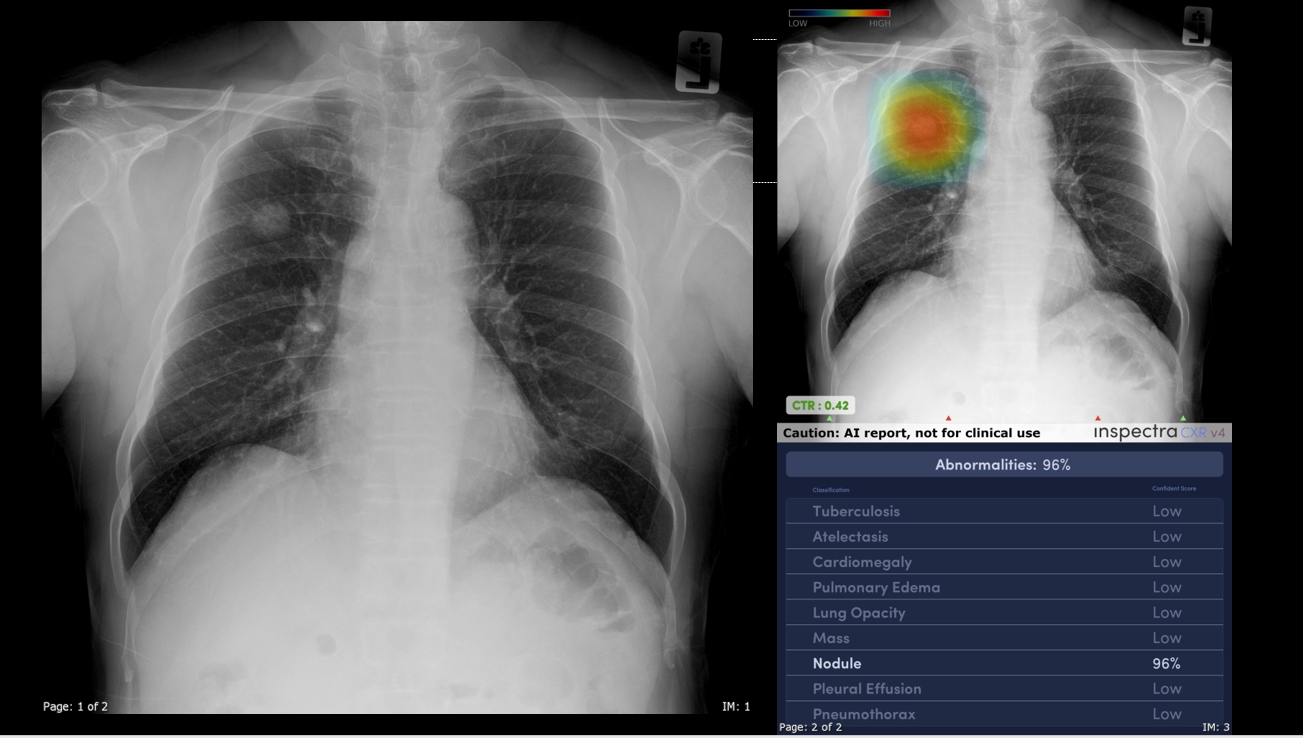

“Inspectra CXR” เทคโนโลยีปัญญาประดิษฐ์ (AI) ที่เข้ามาช่วยแพทย์ในการคัดกรองความผิดปกติรอยโรคที่สำคัญหลายอย่างในภาพเอกซเรย์ปอด และตัวระบบ AI ช่วยแยกความรุนแรงของผู้ติดเชื้อ ทำให้สามารถบ่งชี้ผู้ที่มีความจำเป็นจะต้องได้รับการรักษาอย่างเร่งด่วนได้อย่างชัดเจน

Inspectra CXR ได้รับการพัฒนามาจากภาพถ่ายรังสีทรวงอกกว่า 1.9 ล้านภาพ โดย 60% เรียนรู้จากภาพถ่ายของประชากรไทยและเอเชีย ทำให้ AI สามารถเรียนรู้และจดจำลักษณะทางกายวิภาคและรูปแบบรอยโรคที่เฉพาะเจาะจงได้อย่างแม่นยำ เป็น AI ที่เข้าใจร่างกายคนเอเชีย และใช้เวลาในการวิจัยพัฒนามากว่า 2 ปี เพื่อวินิจฉัยความผิดปกติที่พบได้ทั่วไปจากภาพถ่ายรังสีทรวงอกได้ถึง 8 สภาวะ และผลลัพธ์ที่ได้มีความแม่นยำ 97% จนได้รับการยอมรับจากแพทย์ผู้ใช้งานในวงกว้างทั้งในและต่างประเทศ

Inspectra CXR วิเคราะห์ความผิดปกติได้ 8 สภาวะ ดังนี้

- เงาทึบในปอด ความทึบแสงในปอด (Lung Opacity)

- ก้อนเนื้อผิดปกติ (Mass)

- ก้อนขนาดเล็กในปอด (Nodule)

- ภาวะน้ำท่วมปอด (Pulmonary Edema)

- ภาวะปอดแฟบ (Atelectasis)

- ภาวะหัวใจโต (Cardiomegaly)

- ภาวะน้ำในช่องเยื่อหุ้มปอด (Pleural Effusion)

- วัณโรค (Tuberculosis)

โดยการใช้งานในโรงพยาบาลจะเป็นการเชื่อมต่อระบบ Inspectra CXR เข้ากับระบบสารสนเทศของโรงพยาบาล ให้บริการได้ตลอด 24 ชั่วโมง ทำให้สามารถใช้งานระบบได้อย่างสะดวก ทำให้ช่วยลดระยะเวลาของแพทย์รังสีในการอ่านภาพถ่ายรังสีทรวงอกได้มากถึงร้อยละ 70